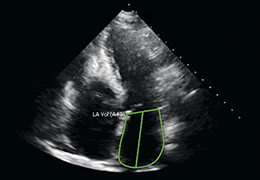

Better understanding of a condition, disease or diagnosis

Ability to clearly see the condition or disease

Better understanding of treatment options

Better grasp of treatment progress by comparing scans over time

Performs 3D reconstruction and volume rendering.